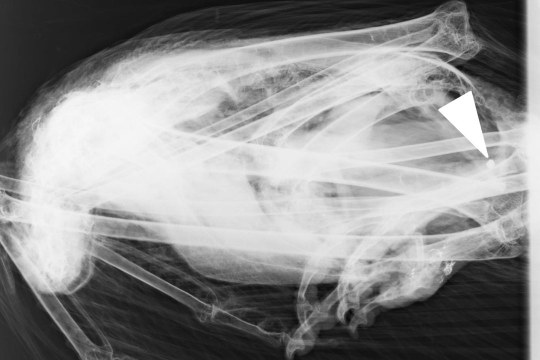

Röntgenbild Gänsegeier | © LMU München © LMU München

Röntgenbild des Gänsegeiers mit dem Befund von Bleigeschoss.

Bei der Untersuchung des Gänsegeiers am LGL stellte sich heraus, dass sich im Gewebe des Greifvogels ein stecknadelkopf-großes bleihaltiges Geschoss von rund fünf Millimetern Größe und nicht einmal einem Gramm Gewicht befand. „Damit ist erneut bewiesen, dass Blei selbst in geringsten Mengen in der Lage ist, auch einen bis zu zehn Kilo schweren und über einen Meter großen Geier zu töten“, erklärt Andreas von Lindeiner. Laut LGL-Befund wird bei Tieren schon ab 2–10mg/kg von einer Bleivergiftung gesprochen. „Die Analysewerte der Leber des Gänsegeiers ergaben eine Belastung mit 22 Milligramm Blei pro Kilo Gewebe“, erklärt der LBV-Biologe.